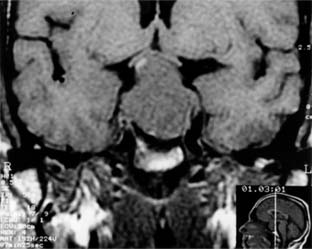

The anterior lobe of the pituitary gland is the site of origin of pituitary tumors (Figure 14-26). Symptoms and signs include loss of vision, field changes, pituitary dysfunction, extraocular nerve palsies, and evidence on CT scan or MRI of sellar and suprasellar tumor.

Figure 14-26

Figure 14-26: Coronal MRI showing large pituitary adenoma elevating and distorting the optic chiasm.